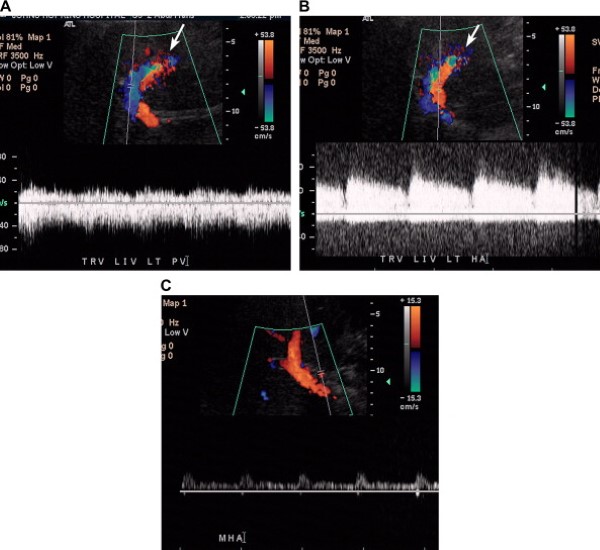

Nguyên nhân hiếm gặp của đảo ngược dòng chảy trong hệ tĩnh mạch cửa là rò động-tĩnh mạch [14]. Các dị dạng động-tĩnh mạch bẩm sinh rất hiếm và phần lớn các rò động tĩnh mạch là do can thiệp (tai biến của sinh thiết gan) hoặc chấn thương. Đôi khi rò kết hợp với tổn thương khu trú [14]. Trên siêu âm, nhánh tĩnh mạch cửa có dòng đảo chiều, trong khi đó động mạch gan có dòng chảy rối với tốc độ tâm trương tăng và RI thấp (Hình 7) [15]. Thông thường, RI của động mạch bị rò thường giảm 30% đến 40% so với động mạch ở các thùy bình thường [15].

Hình 7. Rò động-tĩnh mạch ở bệnh nhân nam 26 tuổi bị viêm gan C, trước khi siêu âm vài tháng đã sinh thiết. (Hình A) Ảnh siêu âm màu và duplex Doppler phát hiện ngành trái tĩnh mạch cửa có dòng chảy đảo chiều. Lưu ý có chảy rối và có khảm màu khu trú (mũi tên). (Hình B) Động mạch gan trái có dòng chảy rối, tốc độ tâm trương tăng so với động mạch gan chính. Cũng lưu ý ổ khảm màu. (Hình C) Ảnh duplex Doppler và màu của thân tĩnh mạch cửa và động mạch gan cho thấy dòng chảy đẩo chiều ở tĩnh mạch và dòng chảy bình thường ở động mạch.